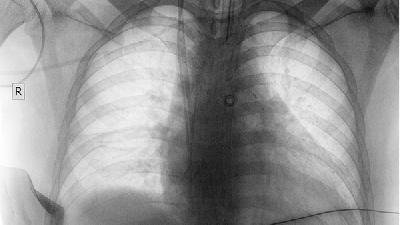

肺气肿的特征是用力时会发生气短、气促的现象。这种呼吸困难是由于肺部组织失去弹性所造成的。病人呼气时需费很大的力气。结果造成不新鲜的空气滞留于肺中,使氧气中二氧化碳无法交换。

常见肺气肿病人稍一活动就气喘如牛,紧接着有些人还会拼命咳嗽。通常,肺气肿病人多为老年,但也可能在年轻或中年时开始。长期患肺病如慢性支气管炎或哮喘病患者容易发生肺气肿。它与遗传也有一定有关,男性患者比女性患者多,有些人因血清蛋白质缺乏而得此病;然而,大部分的病例都是与抽烟有关。如果你有肺气肿,又是老烟枪,那你必须戒烟。抽烟会加速肺气肿的恶化,最后将致命。肺气肿目前尚无法治愈,它与哮喘一并被列为一种慢性阻塞性肺病。

肺气肿症状主要表现为早期活动后气短、进展期持续性呼吸困难、终末期呼吸衰竭伴并发症。 1、早期表现: 轻度活动后气...

肺气肿常见症状包括气短、慢性咳嗽、胸闷、乏力等,病情发展可能出现桶状胸、体重下降等体征。 1、气短 早期表现为活...